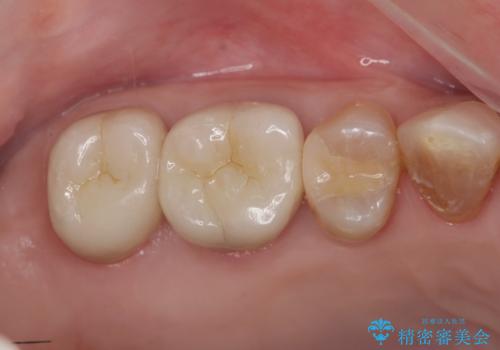

歯周ポケットの除去と再補綴治療

歯周ポケットの除去を歯周外科により行ったのち精度が高く清掃のしやすいセラミック治療による再補綴を行います。

- 42.9万円(ジルコニアクラウン×2・仮歯×2 歯周外科)費用は治療当時の料金となります